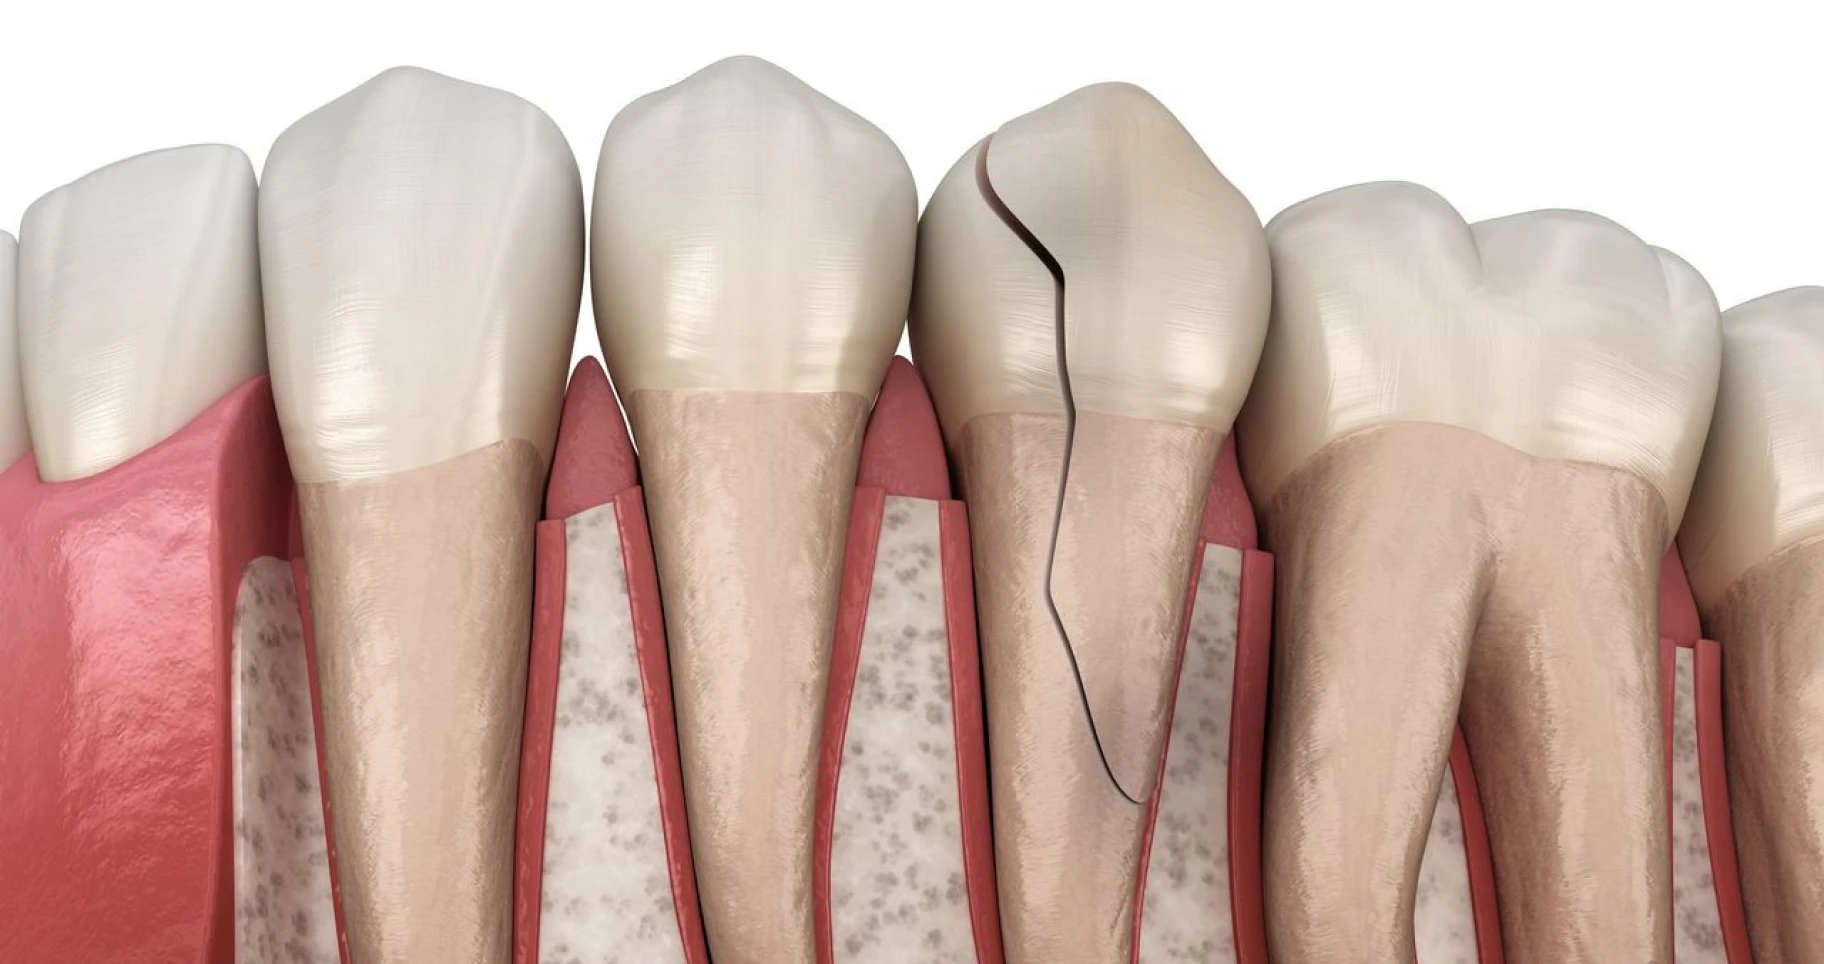

03/09/2024

Dent fissurée : causes, symptômes et solution à Toulouse

Que faire quand on a une dent fissurée ?